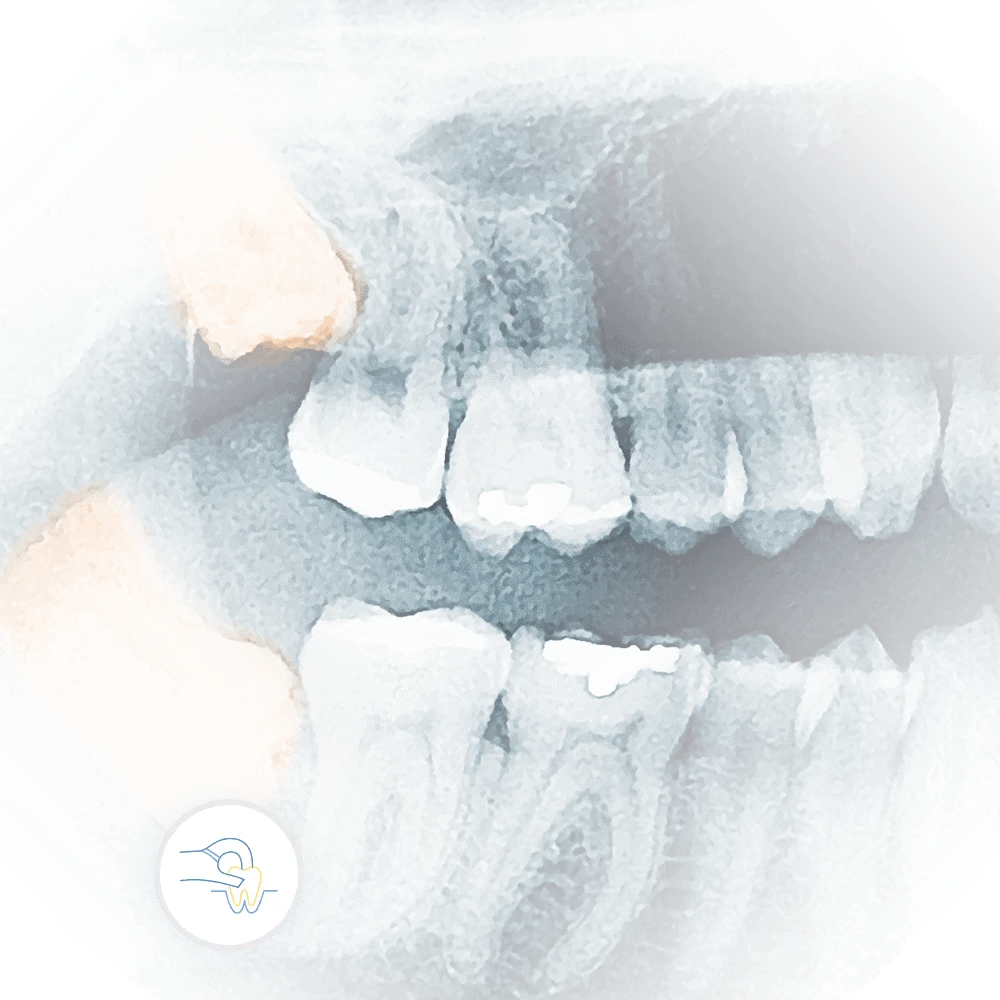

Root canal therapy involves removing the infected or damaged pulp from inside the tooth, cleaning and disinfecting the area, and then sealing it to prevent further infection. It's incredible to witness the transformation in our patients, from arriving in pain and discomfort to leaving our office relieved and on the path to recovery. At Vartanian Dental Group, we are committed to providing top-quality care, and I'm proud to be part of a team that helps patients overcome their fears and restore their dental health. Root canals may have a daunting reputation, but with our compassionate approach and expertise, we make the experience as smooth and stress-free as possible.